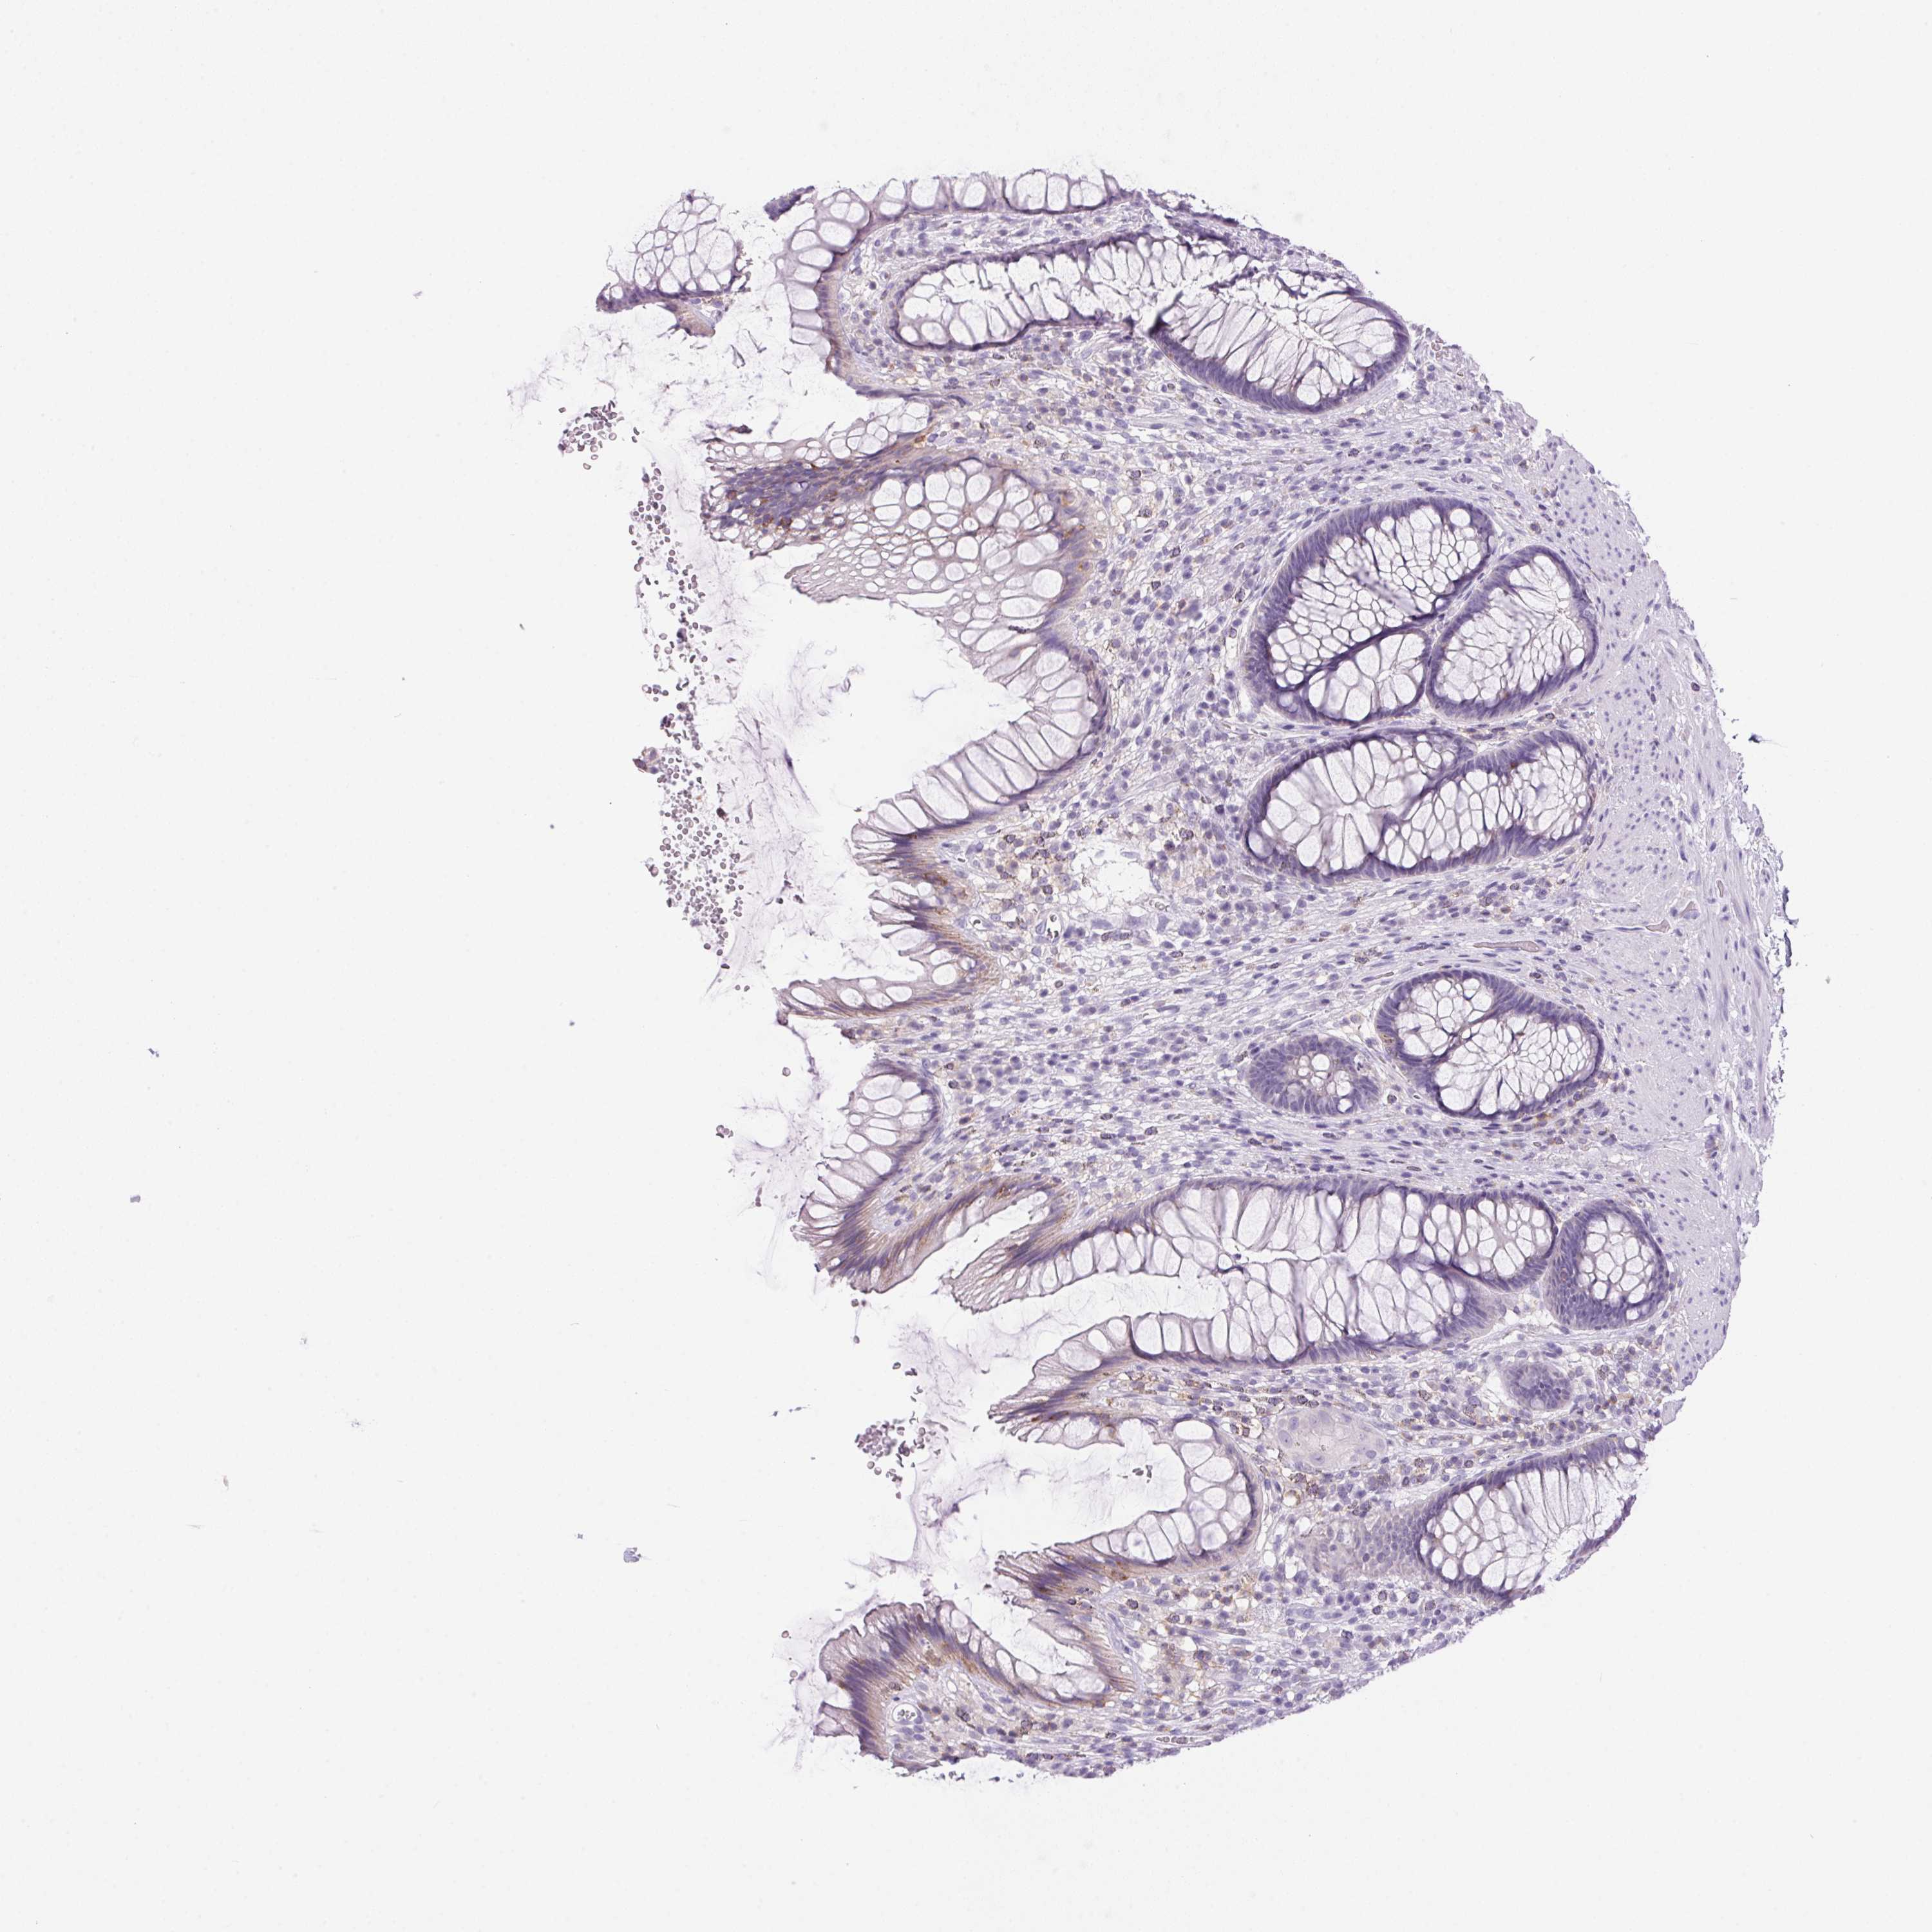

S100A2